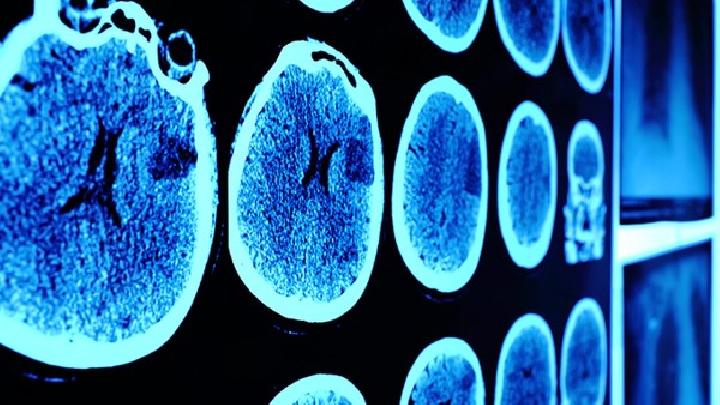

化脓性脑膜炎

化脓性脑膜炎是由于细菌所致的软脑膜、蛛网膜、脑脊液及脑室的急性炎症反应,常常与脑脓肿脑膜炎...

化脓性脑膜炎是由各种化脓性细菌感染引起的急性脑膜炎症,是儿童,尤其是婴幼儿时期常见的神经系...